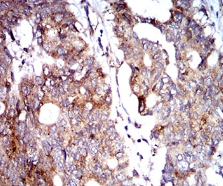

| AC1297 | BNIP3 Mouse Monoclonal antibody[6A5F7] | 100ug | $367 | 10days |

| AC1297 | BNIP3 Mouse Monoclonal antibody[6A5F7] | 200ug | $660.6 | 10days |